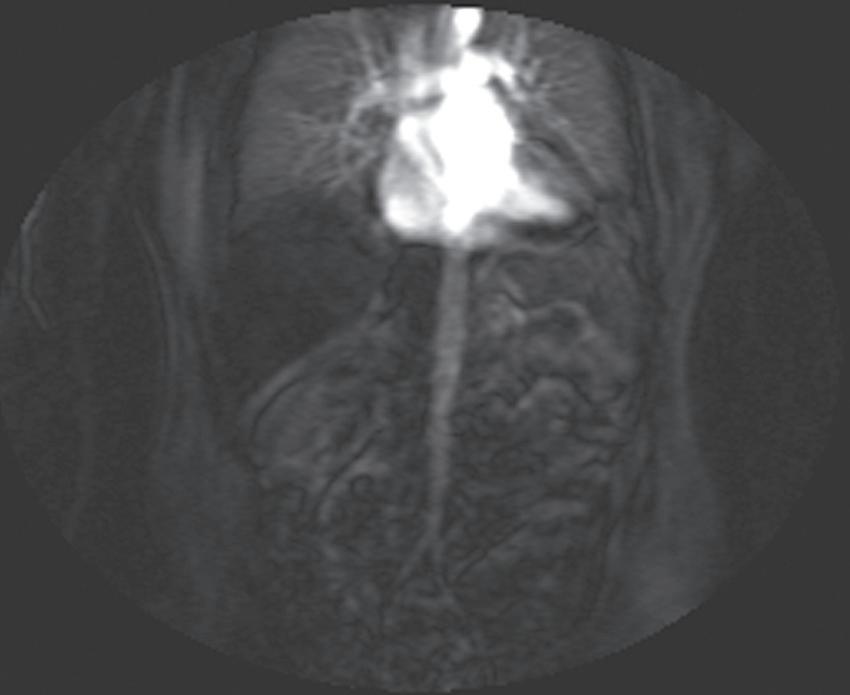

Real-time viewing of contrast transit (Bolus Track, Philips; CARE Bolus, Siemens; SmartPrep, GE; VisualPrep, Toshiba) involves careful monitoring by the technologist of serial large field-ofview (FOV) GE images after administration of the entire bolus of contrast (see Fig. 1.17). Transit of gadolinium through the superior vena cava (SVC) into the right heart through the pulmonary circulation and from the left heart into the aorta is portrayed on the monitor cinegraphically. With impending arrival of contrast into the abdominal aorta, the technologist instructs the patient to suspend respiration in preparation to acquire the arterial phase images. Portal phase images (or

FIG. 1.17 Example of Bolus Track timing sequence to initiate the dynamic acquisition. Selected serial coronal large field-of-view gradient-echo images obtained immediately after the intravenous administration of gadolinium (A–D) reveal the inflow of gadolinium into the superior vena cava (SVC; A), the right ventricle (B), through the pulmonary outflow tract and into the pulmonary arterial system (C), and into the thoracic aorta, down the abdominal aorta (D).